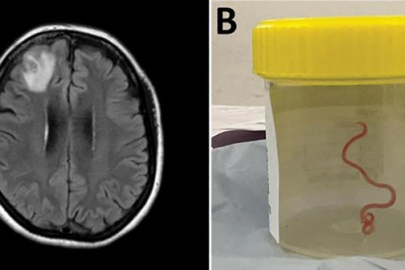

Avustralya'nın başkenti Canberra'da ameliyata alınan bir kadının beyninden 8 santimetre uzunluğunda “canlı solucan” çıkarıldı. Bunun dünyada "bir insanda görülen ilk vaka" olduğu belirtildi.

https://www.sozbursa.com